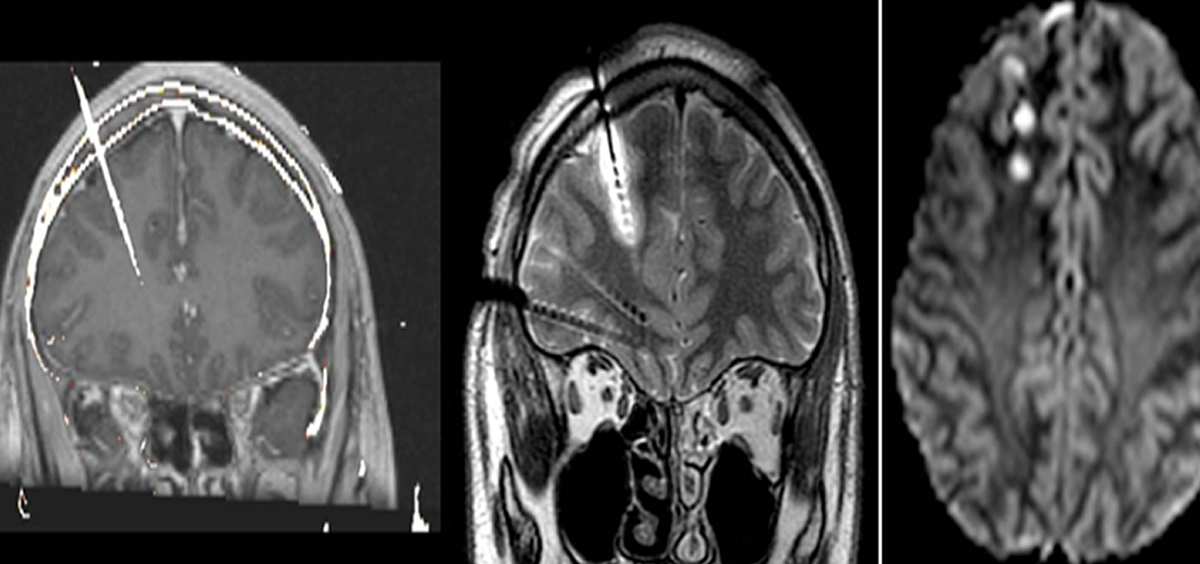

(Imágenes de una resonancia magnética que muestran el procedimiento de esta técnica. Foto. Ruber Internacional)

Se trata de un método mínimamente invasivo de monitorización electrofisiológico que registra la actividad eléctrica del cerebro. En primer lugar, se insertan electrodos en zonas de la corteza cerebral y, a partir de los registros obtenidos, se realiza un mapa en tres dimensiones del foco epiléptico, que ayuda a una exacta localización de la zona afectada para realizar la termocoagulación o la cirugía.

Una vez localizado el foco epiléptico, se procede a la termocoagulación, que se vale de los mismos electrodos de la E-EEG para destruirlo, así como a sus vías de propagación, mediante una corriente eléctrica regulada a causa de su ablación térmica.